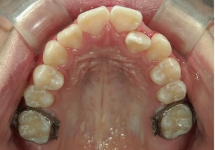

クワドヘリックス(QH)

上顎骨の横幅を広げる効果があり、上顎の幅が狭い時や、歯の生えるスペースが足りない時に使用します。症例2の場合、内側に入っていた左上2番が、装置に押し出されて正常な位置に移動しました。